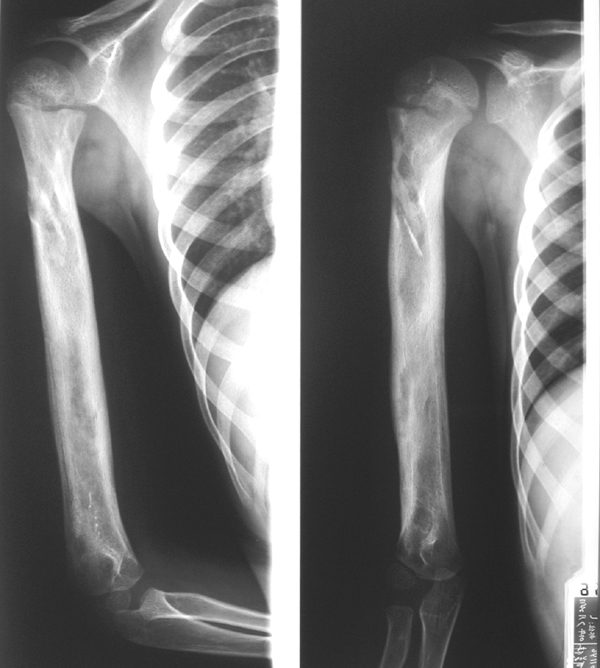

骨肉瘤:最常见的恶性骨肿瘤

临床:1、年龄:青少年(11-20岁占50%),男多于女;2、部位:以膝关节、肱骨上端多见。;;发生于干骺端。

影像学表现:1.源于骨髓腔的不规则的骨破坏和骨增生;2.骨皮质破坏,骨膜增生–葱皮样、放射状,Codman三角(袖口征)-骨膜增生被破坏形成

3.软组织肿块,其内见肿瘤骨(诊断骨肉瘤要点)。云絮状、针状、放射状、斑块状

4.不累及关节;5.病理性骨折

桡骨上段成骨型骨肉瘤:骨质增生硬化,并有骨膜反应,软组织肿块

股骨下端溶骨型骨肉瘤